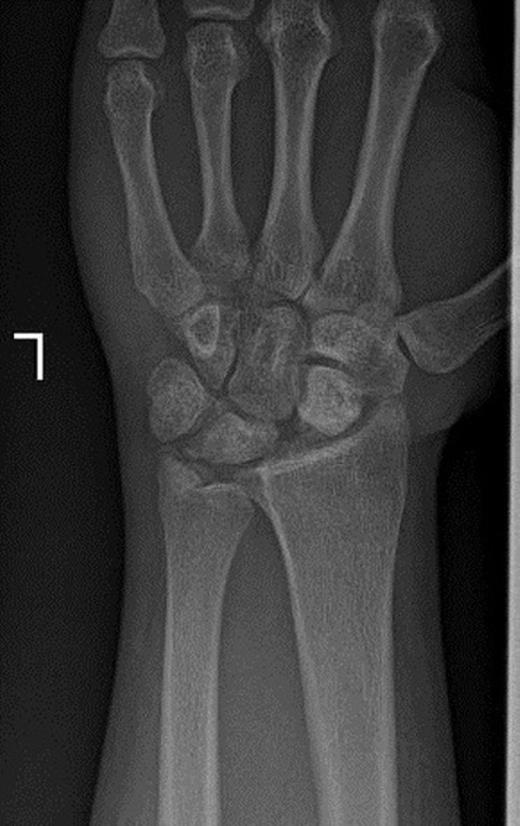

Pins were removed six weeks later, and the cast was discarded ten weeks later. Active and passive range of wrist motion and muscle strengthening exercises were begun. The patient didn’t refer for follow-ups. After two years, he came back with pain, limited motion, and weakness in grip and grasp. Radiographs showed osteonecrosis of lunate and proximal scaphoid. Also, static scapholunate dissociation with signs of mild arthritis was obvious (Figure 2a & 2b).

Posteroanterior and lateral radiographs of left wrist two years after operation show increased density of lunate and proximal scaphoid with subtle arthritic changes. Scapholunate dissociation (Terry-Thomas sign) and dorsal intercalated segment instability are seen.